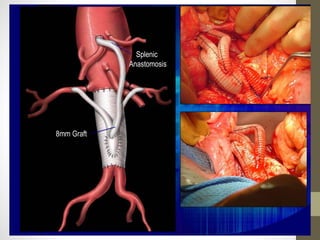

8mm Graft

Splenic

Anastomosis

Combined open and endovascular treatment of thoracoabdominal aortic pathologies: a

systematic review and meta-analysis

Konstantinos G. Moulakakis1,2, Spyridon N. Mylonas1, Constantinos N. Antonopoulos1,

Christos D. Liapis1

• Hybrid procedures have several advantages over conventional open

repair

• avoiding thoracotomy,

• single-lung ventilation,

• aortic cross-clamping,

• minimizing end-organ ischemia

• the hybrid technique is still associated with

• a considerable morbidity and mortality rate.

• have a role in those patients anatomically unsuitable for fenestrated and side

branched endografts.

• good option for elderly, high-risk patients

• should be reserved for high volume centers with accumulated experience and

high standards of perioperative management

• further concern is the durability and long-term outcome which is

related either to endograft complications